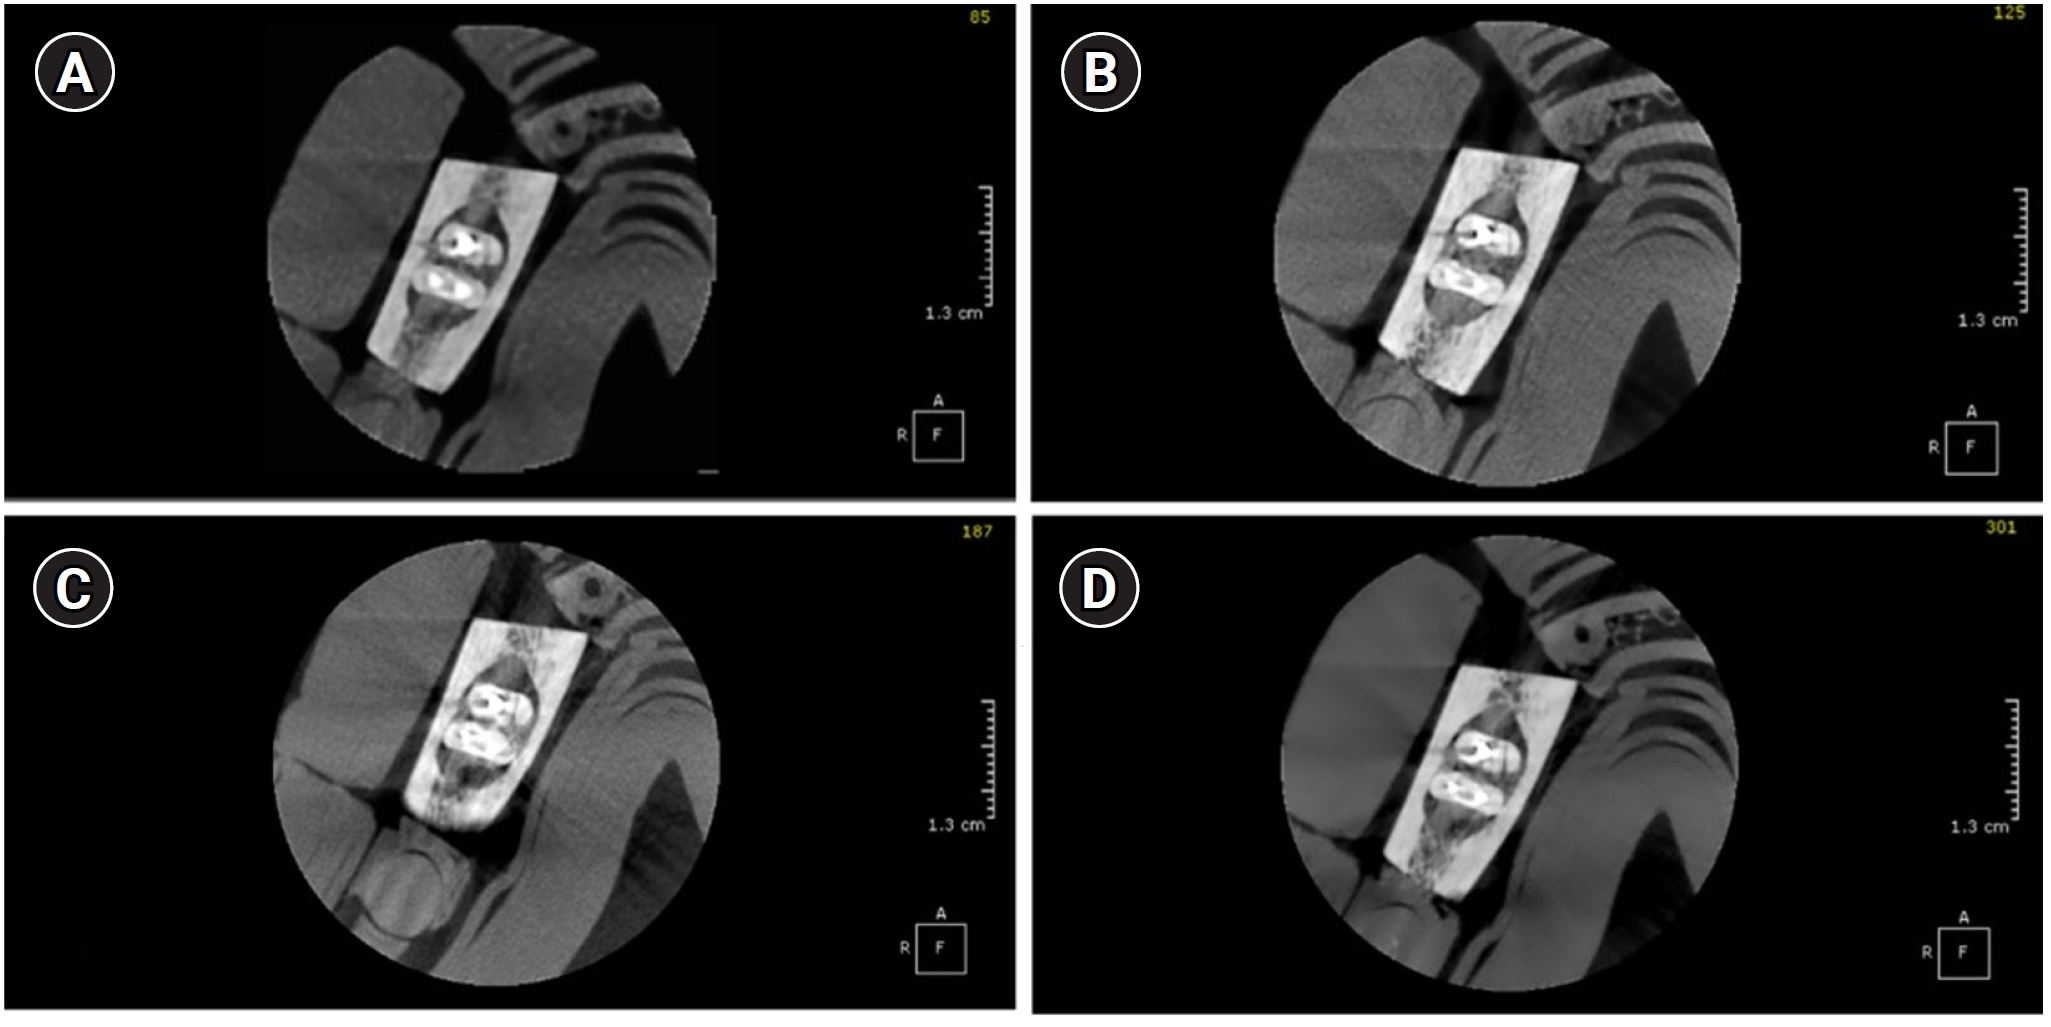

Table 2 highlights the percentage of correct diagnoses (hits) for each examiner, stratified by CBCT acquisition protocol and the presence of metallic posts. A statistically significant difference was observed in examiner 1’s evaluations. For teeth with metal posts, the low-resolution protocol resulted in significantly fewer correct diagnoses (75%) compared to the standard-resolution (95%), high-resolution (95%), and endo-resolution (95%) protocols (p = 0.028). For teeth without metallic posts, diagnostic performance remained consistently high across all acquisition protocols, with accuracy values generally above 0.85 for all examiners. Notably, the endo-resolution protocol achieved 95% or higher accuracy for most examiners, emphasizing its superior diagnostic potential in this scenario. Figures 1 and 2 show axial cone-beam computed tomography slices of the sample teeth without and with post, respectively, acquired on the four protocols.

Axial cone-beam computed tomography slices of a sample tooth without post acquired on the four protocols. (A) Low dose resolution, (B) standard resolution, (C) high resolution, and (D) endo resolution.